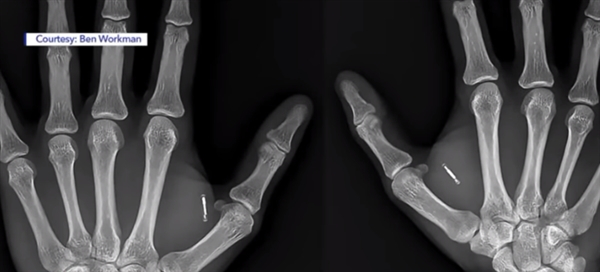

据外媒报道,美国犹他州男子Ben Workman是一位乐于进行人体改造的极客,在先后将门禁芯片、工卡等芯片植入体内后,Workman将新目标锁定在了Model 3的车钥匙上。

由于车钥匙芯片较大,Workman遍寻兽医、外科医生,居然没人愿意接单。最后还是在一家纹身打孔专业工作室里完成了植入。